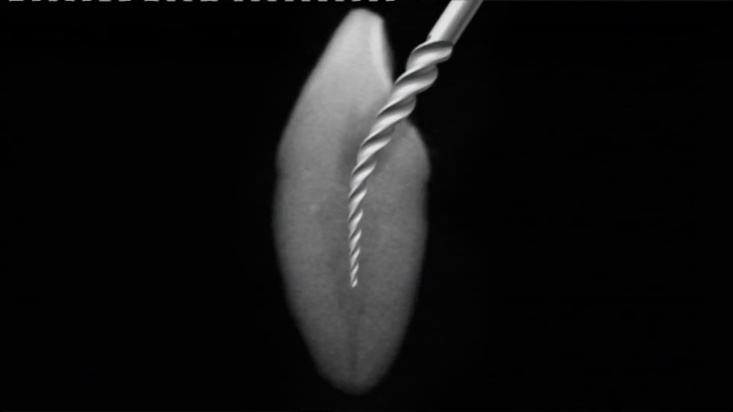

Сл. 19.1 Графички приказ на стресот на свиткување.